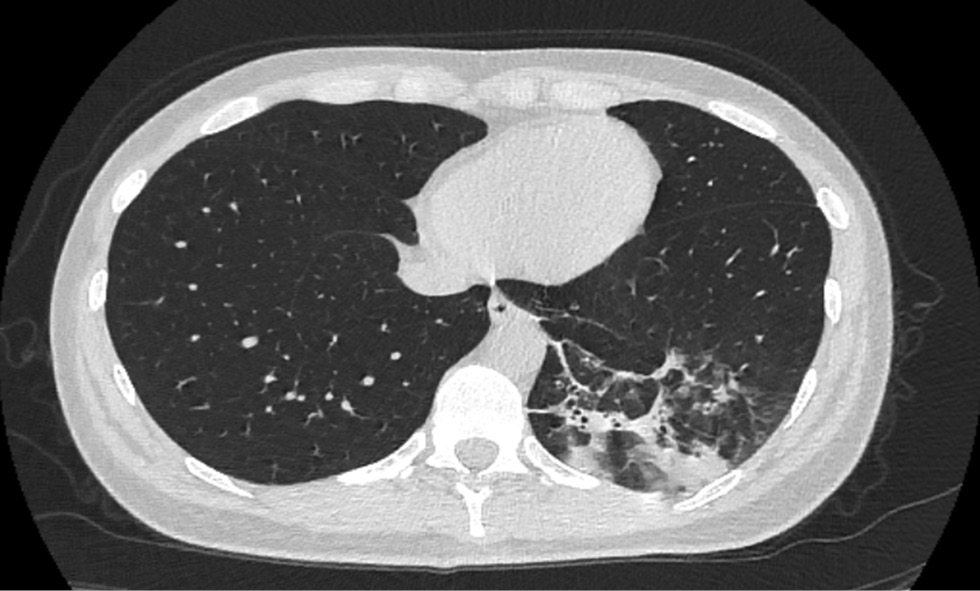

Patient M., 50 years old, was admitted to the St. Petersburg Clinical Hospital of the Russian Academy of Sciences on 06/07/2020 with a referral diagnosis of bilateral ovarian tumors. Ovarian cancer was questionable. Lymphadenopathy. Adenomyosis. Myoma of the uterus. Condition after viral community-acquired pneumonia caused by the SARS-CoV-2 virus in April 2020 (lung damage according to computed tomography data ~ 40%) (Fig. 1, 2).

Fig. 1. Computed tomography of the lungs, April 2020 (picture of viral pneumonia caused by the SARS-CoV-2 virus, lung damage ~ 40%)